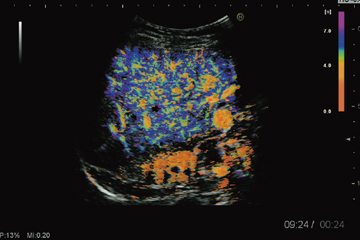

Inflow Time Mapping(ITM)は,輝度解析機能の1つで,Contrast Harmonic Imagingによる造影剤の流入時間差に着目して,各画素の時間的な輝度変化を色付け表示する(図4)。解析画像はさまざまなカスタマイズが可能で,色付けが変化していく様子を連続的に確認したい場合には,グラデーション表示も可能である。また,解析画像上の不要なノイズ成分を除去する機能も搭載している。